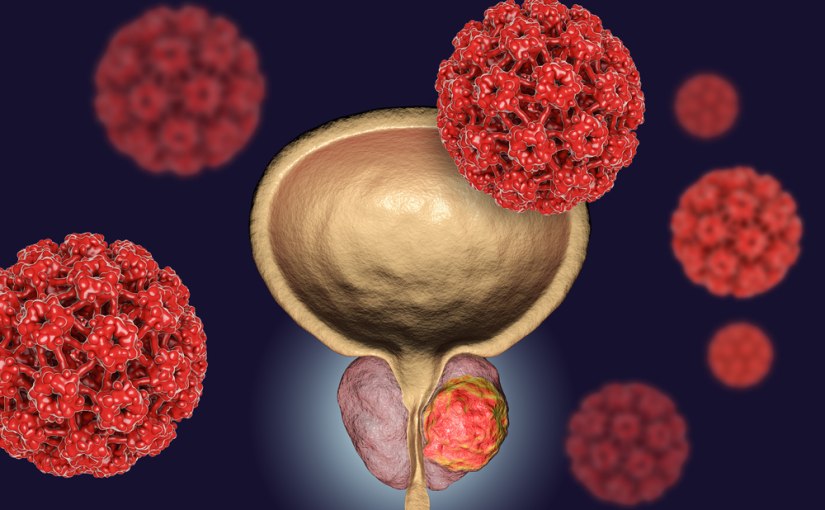

Prostate problems are common in men, especially with age. Conditions like benign prostatic hyperplasia (BPH), prostatitis, and prostate cancer can cause urinary difficulties, frequent urination, or pelvic discomfort. With early diagnosis and advanced treatment options, we offer personalized care to manage prostate health effectively and improve quality of life.